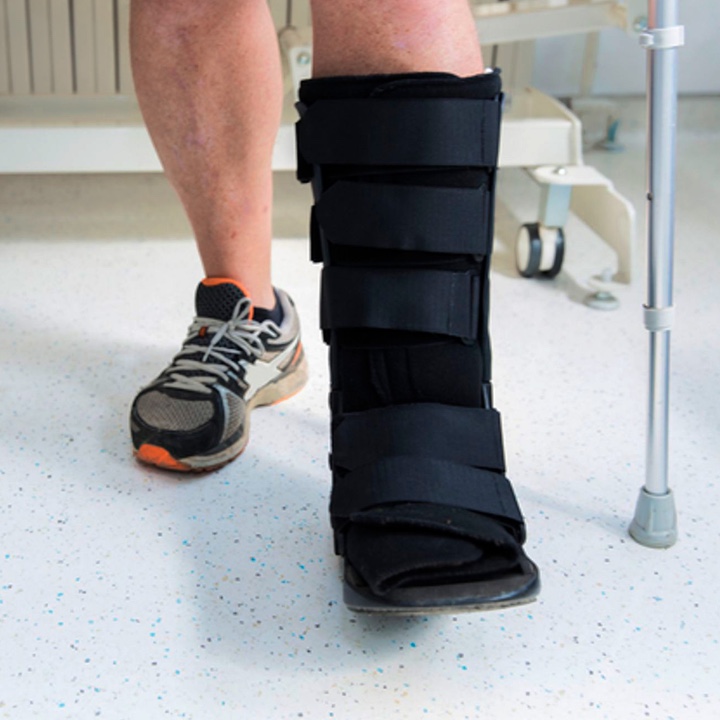

• Get back on your feet quickly in a walking boot1

- Get back on your feet quickly in a boot; many cases within 2 weeks

Get Back on Your Feet Quickly

Recovery From Lapiplasty®

A typical recovery timeline is detailed below. However, timepoints and doctor’s orders vary based on each patient’s condition. Be sure to ask your doctor what your particular recovery protocol will look like.

Within Days

Begin to put some weight on your foot1

Next 4-6 Weeks

Walk in a boot and return to daily activities

At 6-8 Weeks

Transition back into comfortable shoes

At 4-6 Months

Resume most activities and return to normal footwear